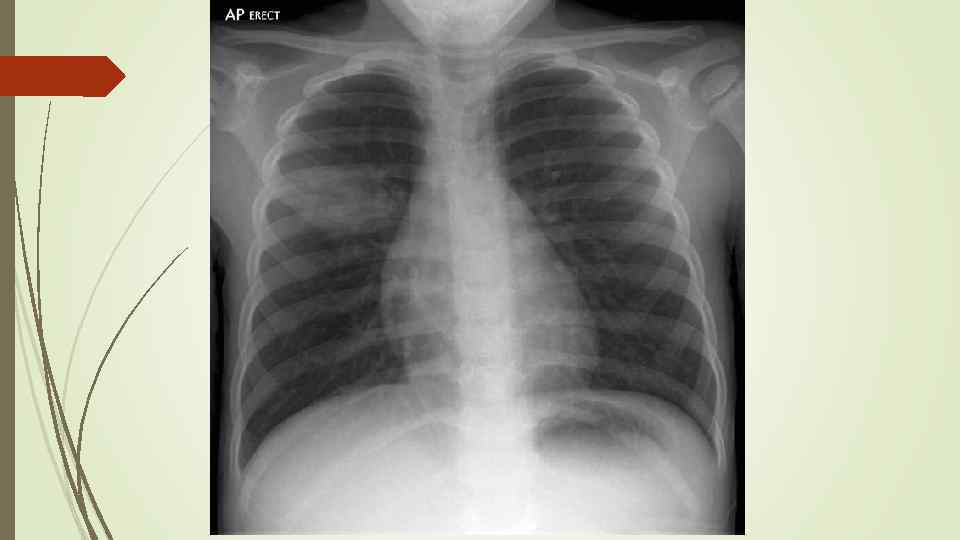

Бронхопневмония Характерно наличие двухсторонних множественных очаговых теней. Контуры очагов нечеткие, интенсивность тени небольшая. Инфильтрация неоднородна. Мелкие, малоинтенсивные очаги не всегда выявляются на снимках. Легочный рисунок усилен на всем протяжении легких. Корни расширены, не структурны. Как правило, отмечается реакция плевры, могут быть и экссудативные плевриты.

Бронхопневмония Характерно наличие двухсторонних множественных очаговых теней. Контуры очагов нечеткие, интенсивность тени небольшая. Инфильтрация неоднородна. Мелкие, малоинтенсивные очаги не всегда выявляются на снимках. Легочный рисунок усилен на всем протяжении легких. Корни расширены, не структурны. Как правило, отмечается реакция плевры, могут быть и экссудативные плевриты.